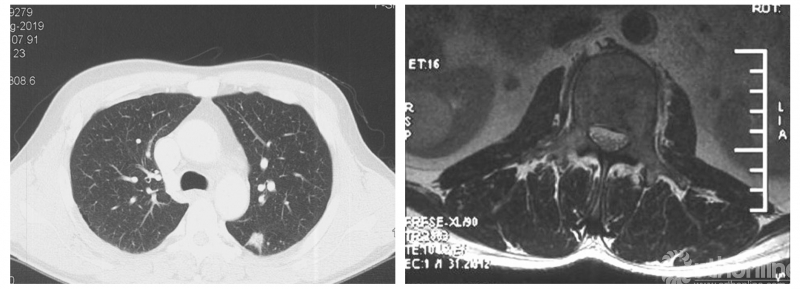

影像学资料

PVP治疗

术后6个月

患者腰椎转移瘤术后9个月,因“腰痛伴右下肢疼痛麻木2个月”再次入院。既往在PVP术后曾行化疗及服用埃克替尼靶向药物维持治疗,查体一般状况良好,自主行走,右大腿前外侧麻木。

入院影像学资料